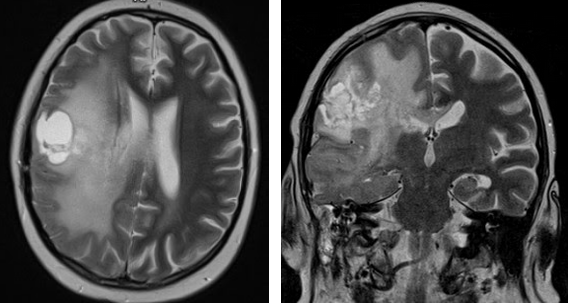

Рисунки 3,4. МРТ головного мозга

Опухоль (глиобластома) правой лобно-теменной области, окруженная выраженной зоной перифокального отека.